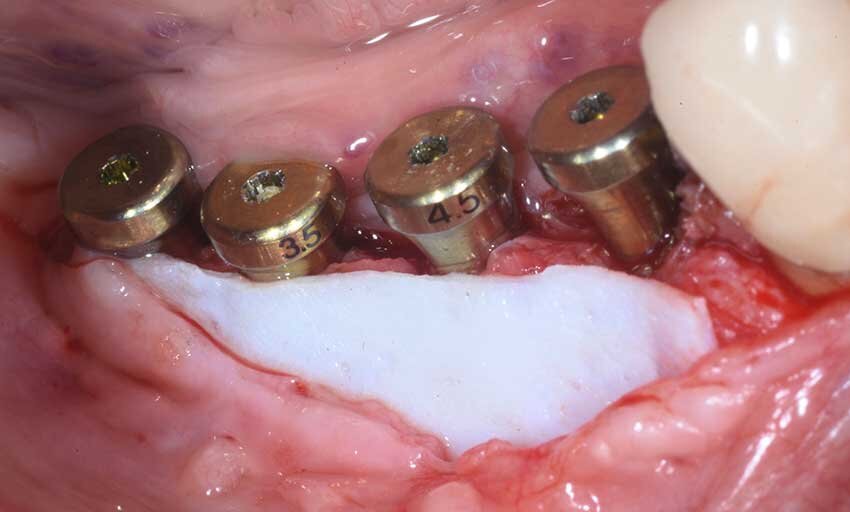

Dopo aver somministrato l’anestesia locale con Articaina con adrenalina 1.200.00 veniva eseguita un’incisone con lama 12 sulla cresta edentula facendo attenzione a dividere l’esigua quantità di gengiva cheratinizzata in maniera equa tra i due lembi, vestibolare e linguale. La cresta esposta confermava quanto osservato sulla CBCT, lo spessore in cresta era di 3 mm nella zona distale al canino e andava ad assottigliarsi fino ad 1 mm nella zona dei molari. In prossimità del sito 46 si trovava un residuo radicolare, che veniva rimosso e nella stessa posizione veniva inserito un impianto di diametro standard (4 mm) mentre gli impianti nei siti dei premolari e del secondo molare erano di diametro ridotto (3.5) (Fig. 4).

La rx post-operatoria evidenzia bene come nel sito 46 l’impianto fosse ancorato all’osso solamente dalla sua porzione apicale, mentre l’immagine clinica (Fig. 5) mostra quanto ognuno dei quattro impianti (Neodent-Straumann) presentasse una evidente deiescenza vestibolare con almeno 5-6 spire esposte fuori cresta e una evidente insufficienza di volume in senso orizzontale (Fig. 6). Per questa specifica situazione clinica si selezionò un materiale (GTO Osteobiol) da innesto con caratteristiche particolari, appiccicoso e capace di creare e mantenere il volume anche in una situazione anatomicamente sfavorevole. Questo bio-materiale è composto da osso suino collagenato associato a un gel termo sensibile (TSV gel) che gli consente di “gellificare” e diventare solido al contatto con l’umidità della bocca. Queste caratteristiche lo rendono facilmente plasmabile al difetto e nello stesso tempo stabile, dalla figura 6 si può notare come questa stabilità consenta di apporre una quantità di materiale adeguato a correggere il difetto della cresta e a proteggere le spire degli impianti altresì esposte (Fig. 7).

Fig. 4 - Rx post-operatorio.

Fig. 5 - Impianti inseriti.